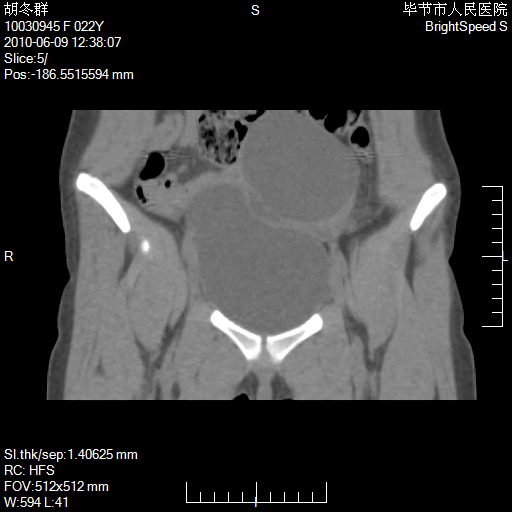

患者23岁,发现腹部包块3月。

盆腔内囊性占位;穿刺或者直接手术拿掉即可,不必紧张。

左侧卵巢囊腺瘤或囊腺癌

盆腔内囊性占位性病变;考虑左侧卵巢囊腺瘤。

有分隔、壁薄,支持考虑左侧卵巢囊腺瘤。

左侧卵巢浆液性囊腺瘤。

支持考虑左侧卵巢囊腺瘤;宫腔积液。

有分隔、壁薄,支持考虑左侧卵巢囊腺瘤。排尿后,膀胱缩小,由于重力作用,肿块下移就到了膀胱位置,很好理解。